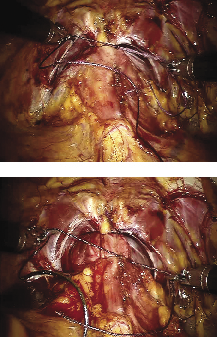

Posterior reconstruction

Posterior reconstruction helps create a posterior plate in which to buffer the anastamosis and reduce bleeding, see Figure 4. Several studies have shown that a proper posterior reconstruction reduces urinary leaks and could also help promote earlier return to pad-free continence.8,9

The left sided VLOC suture is anchored at the 5 o’clock position of the bladder neck. The cut Denonvillier’s fascia and the detrusor muscle are grasped and passed through with the needle. The suture slack is held and pulled upward using a ‘hand over hand’ technique until the part the sutures interlock are within the bladder muscle. The needle is then positioned towards the urethra and the assistant introduces the Foley catheter tip. The needle is then passed through the posterior side of the urethra at the same 5 o’clock position. The suture is pulled through until the interlocked loops abut with the tissue providing resistance, as a knot would. A second bite is then taken from the midline retrotrigonal area behind the bladder followed by a 6 o’clock bite of the periurethral tissue. Special care is made to ensure there is no cephalad traction on the bladder prior to cinching. Finally, a 7 o’clock suture is taken on the bladder-side retrotrigonal tissue again ensuring not to include any mucosa. The left arm of the interlocked V-Loc suture is then lifted cephalad and anteriorly with the left needle driver, while the open right needle driver sat on the bladder tissue to serve as a fulcrum point to avoid tissue tearing. The bladder is thus cinched down with repetitive, short pulls until the bladder neck mucosa is adjacent to the urethral stump with no gap.

Figure 4. Posterior reconstruction. A. The VLOC suture is passed through the bladder-side retrotrigonal area at the 5, 6 and 7 o’clock position and through the periurethral rectourethralis muscle. B. Traction is used on the VLOC suture to cinch down the bladder until its mucosa is adjacent to the urethral stump and no gap is left.